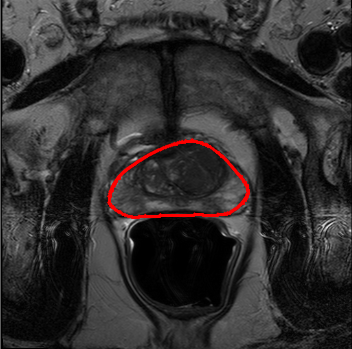

We trained our network on 77 patients. The input images and the manual ground truth annotation are shown in Fig.4. As we have described above, these images were acquired from different patients, and these images include the clinical variability. To evaluate our method, we randomly selected 4 patients with 64 images before training. These images do not take part in training and the prostate has been manually pre-delineated by a radiologist, which were used as the ground truth to evaluate the performance of automatic segmentation. We also selected dice coefficient as the evaluation method[30]. And to validate our method against U-Net and fully convolutional networks (FCNs), we used the same dataset to train and test the U-Net and FCNs.

To intuitively compare the proposed method with U-Net and FCN, the segmentation results of some representative and challenging samples are shown in Fig 5. It can be seen that these prostate images have fuzzy boundaries and the pixel intensity distributions are inhomogeneous both inside and outside of the prostate. Besides, both prostate and nonprostate regions have similar contrast and intensity distributions. All of these phenomenons make the segmentation difficult.